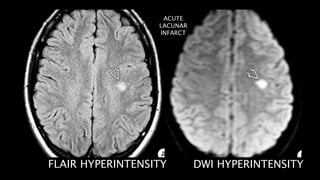

FLAIR HYPERINTENSITY DWI HYPERINTENSITY

• #121 this are the axial FLAIR and DWI images showing another example of acute lacunar infarct in left hemispheric white matter showing FLAIR AND DWI hyperintensity